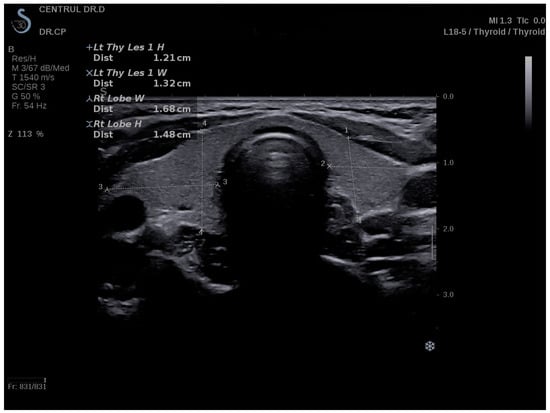

2.4. Conventional Ultrasound and Elastography Examination

3.1. Strain Elastography Measurements